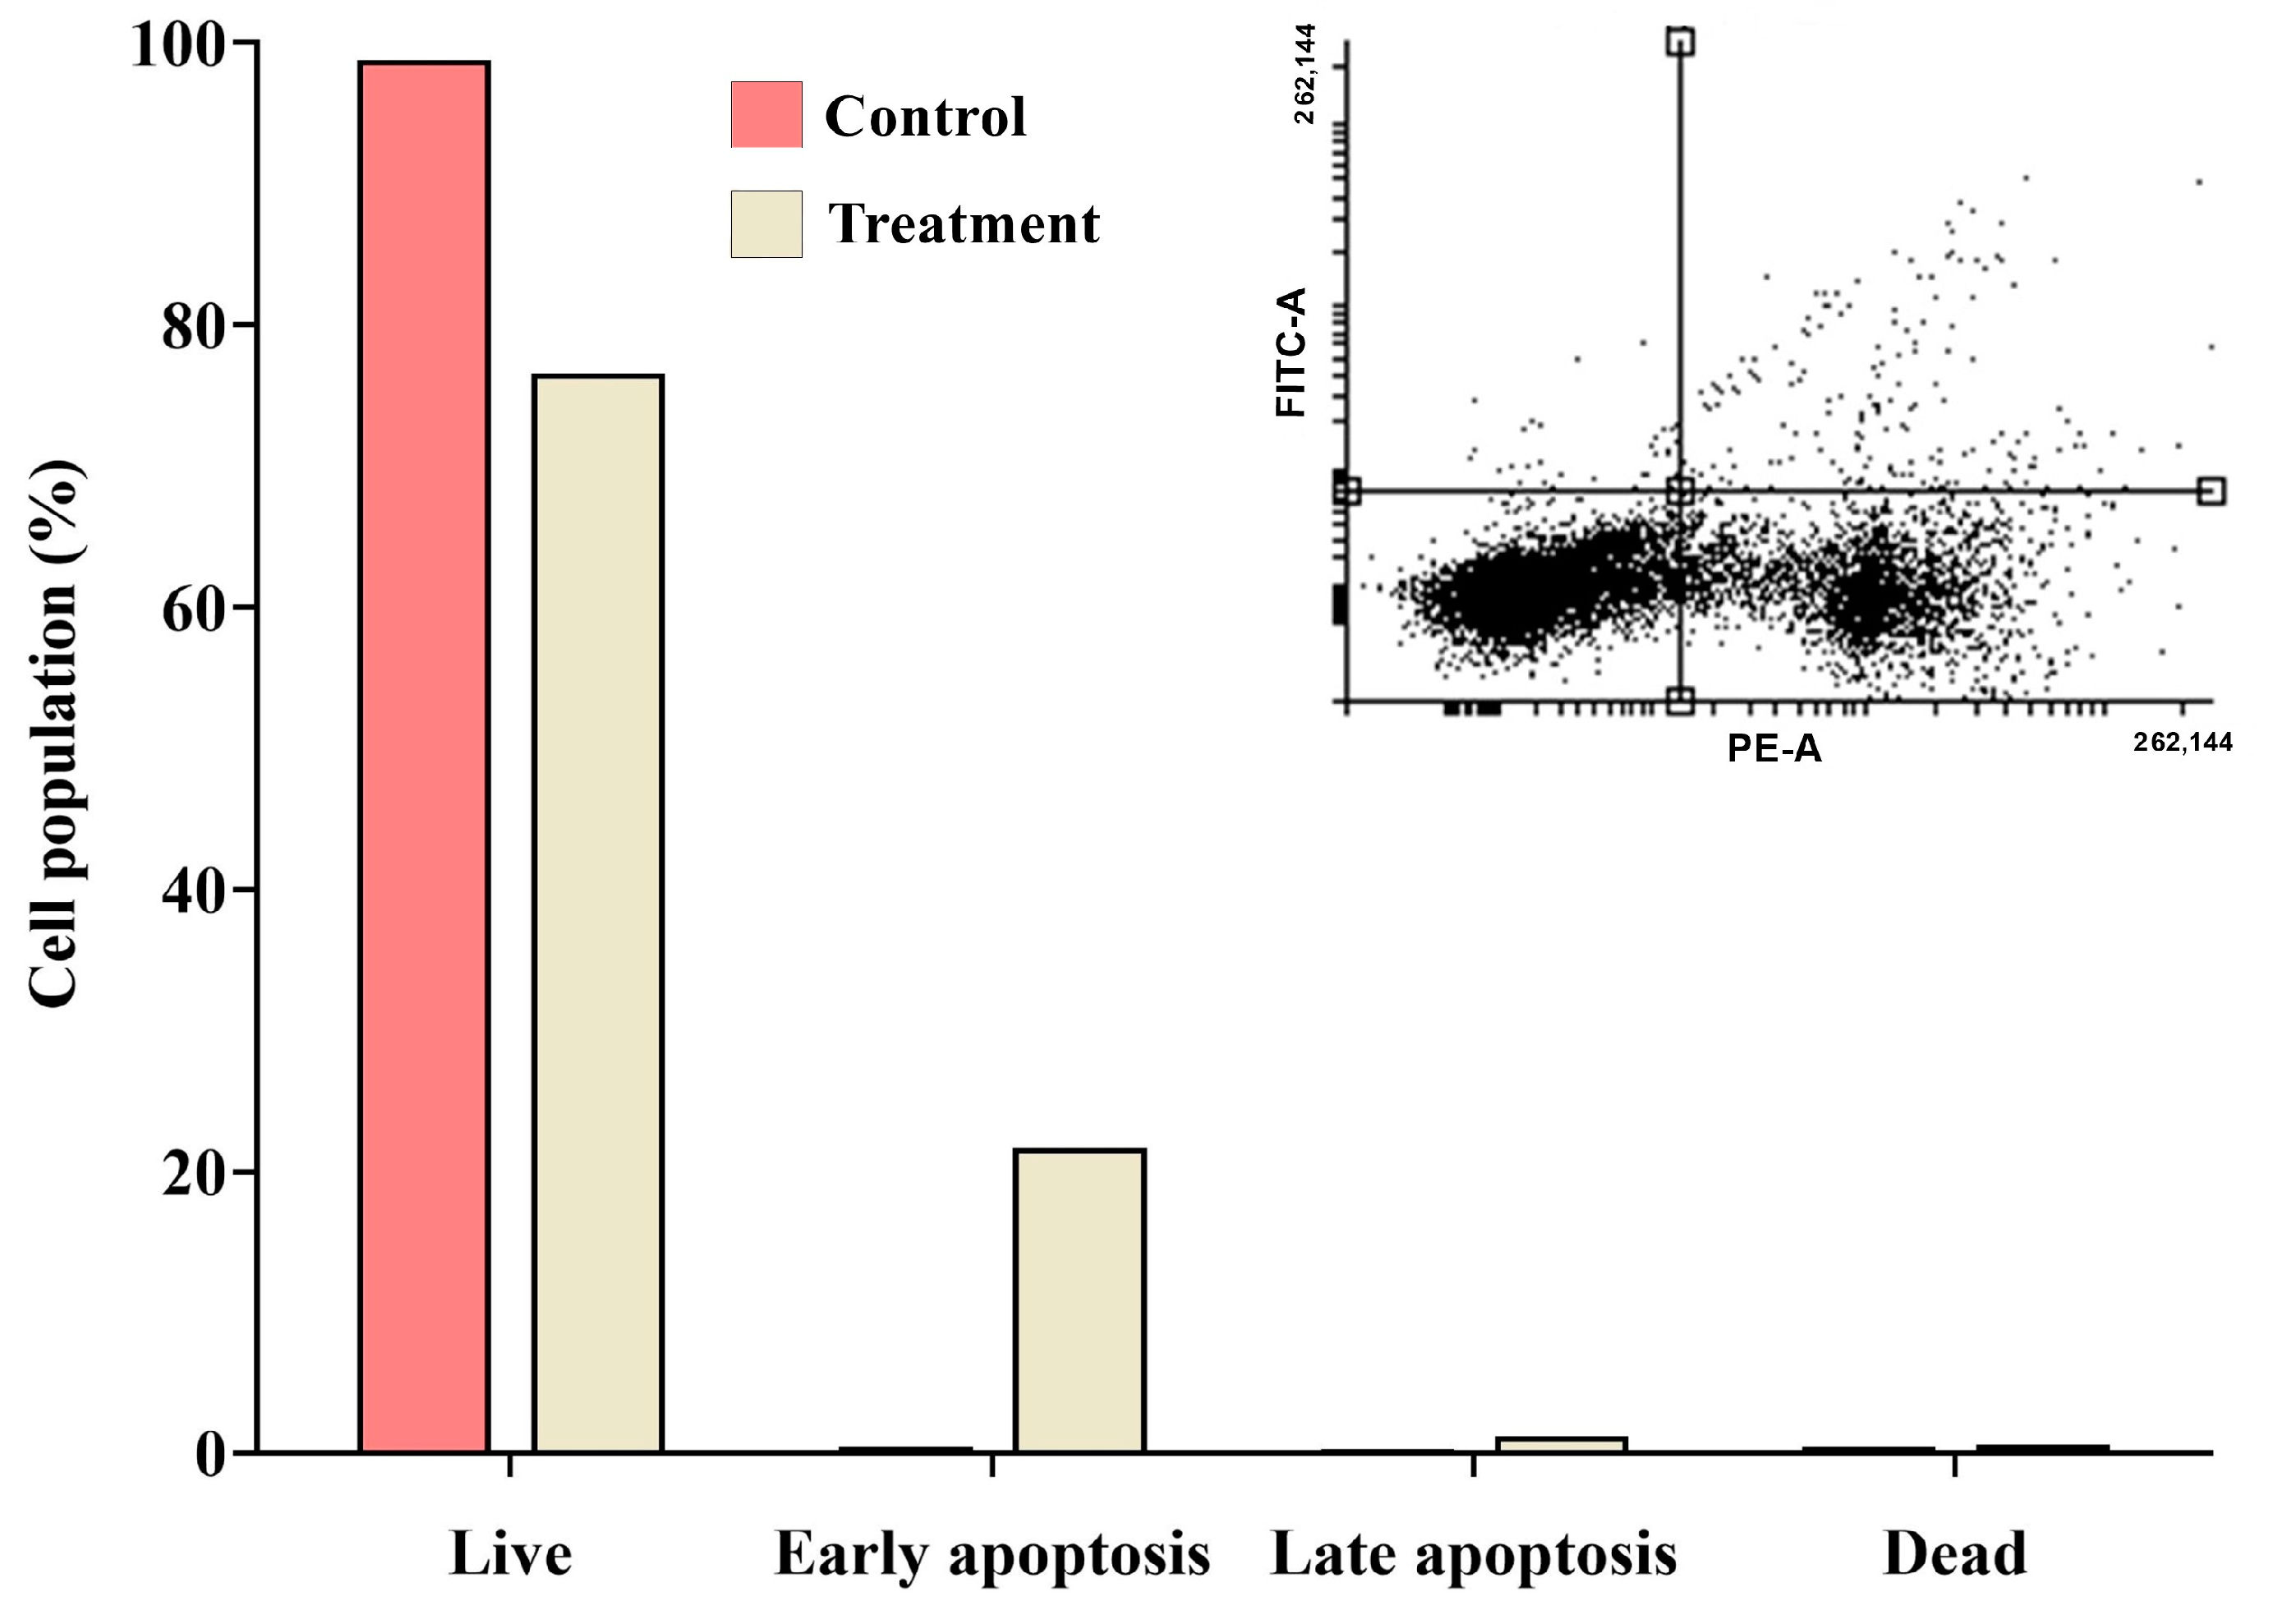

2.9. Detection of Apoptosis Using Propidium Iodide (PI) Staining with Annexin V